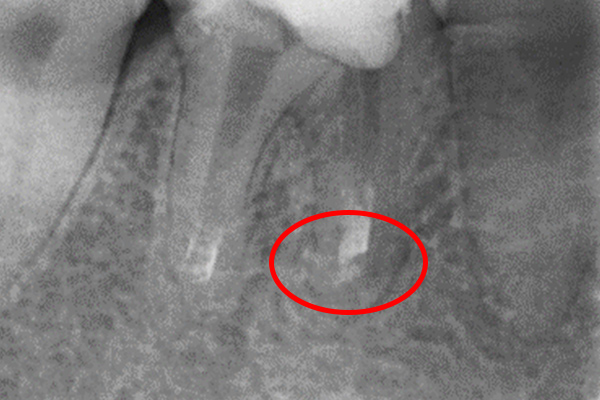

根の横に誤った穴をあけてしまい、気づかずに薬を入れてしまっている。また、器具が破折し、根の先に飛び出ている。

※本来の根管に薬が入ってることがわかります。